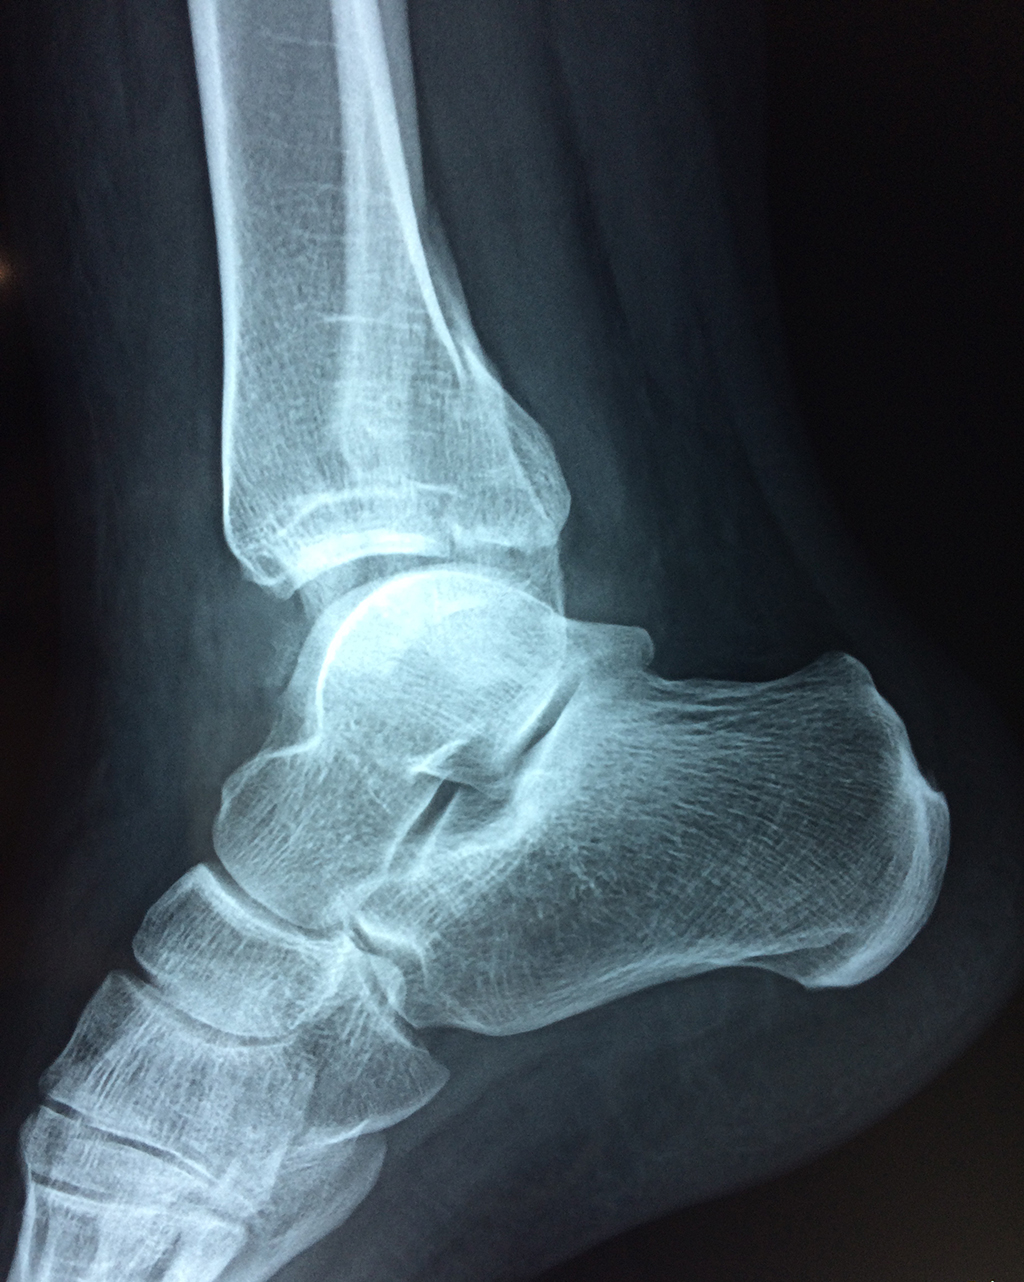

Una fractura de tobillo es la rotura de uno o más de los huesos del tobillo. Estas fracturas pueden ser:

Algunas fracturas de tobillo pueden requerir cirugía si:

- Los extremos de los huesos están desalineados entre sí (desplazados).

- La fractura se extiende hasta la articulación del tobillo (fractura intra-articular).